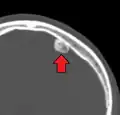

Osteoma of the frontal sinus on CT -